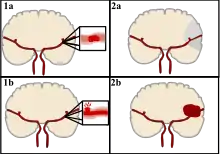

A stroke is a medical condition in which poor blood flow to the brain causes cell death.[5] There are two main types of stroke: ischemic, due to lack of blood flow, and hemorrhagic, due to bleeding.[5] Both cause parts of the brain to stop functioning properly.[5]

Strokes can be classified into two major categories: ischemic and hemorrhagic.[19] Ischemic strokes are caused by interruption of the blood supply to the brain, while hemorrhagic strokes result from the rupture of a blood vessel or an abnormal vascular structure. About 87% of strokes are ischemic, the rest being hemorrhagic. Bleeding can develop inside areas of ischemia, a condition known as "hemorrhagic transformation." It is unknown how many hemorrhagic strokes actually start as ischemic strokes.[2]